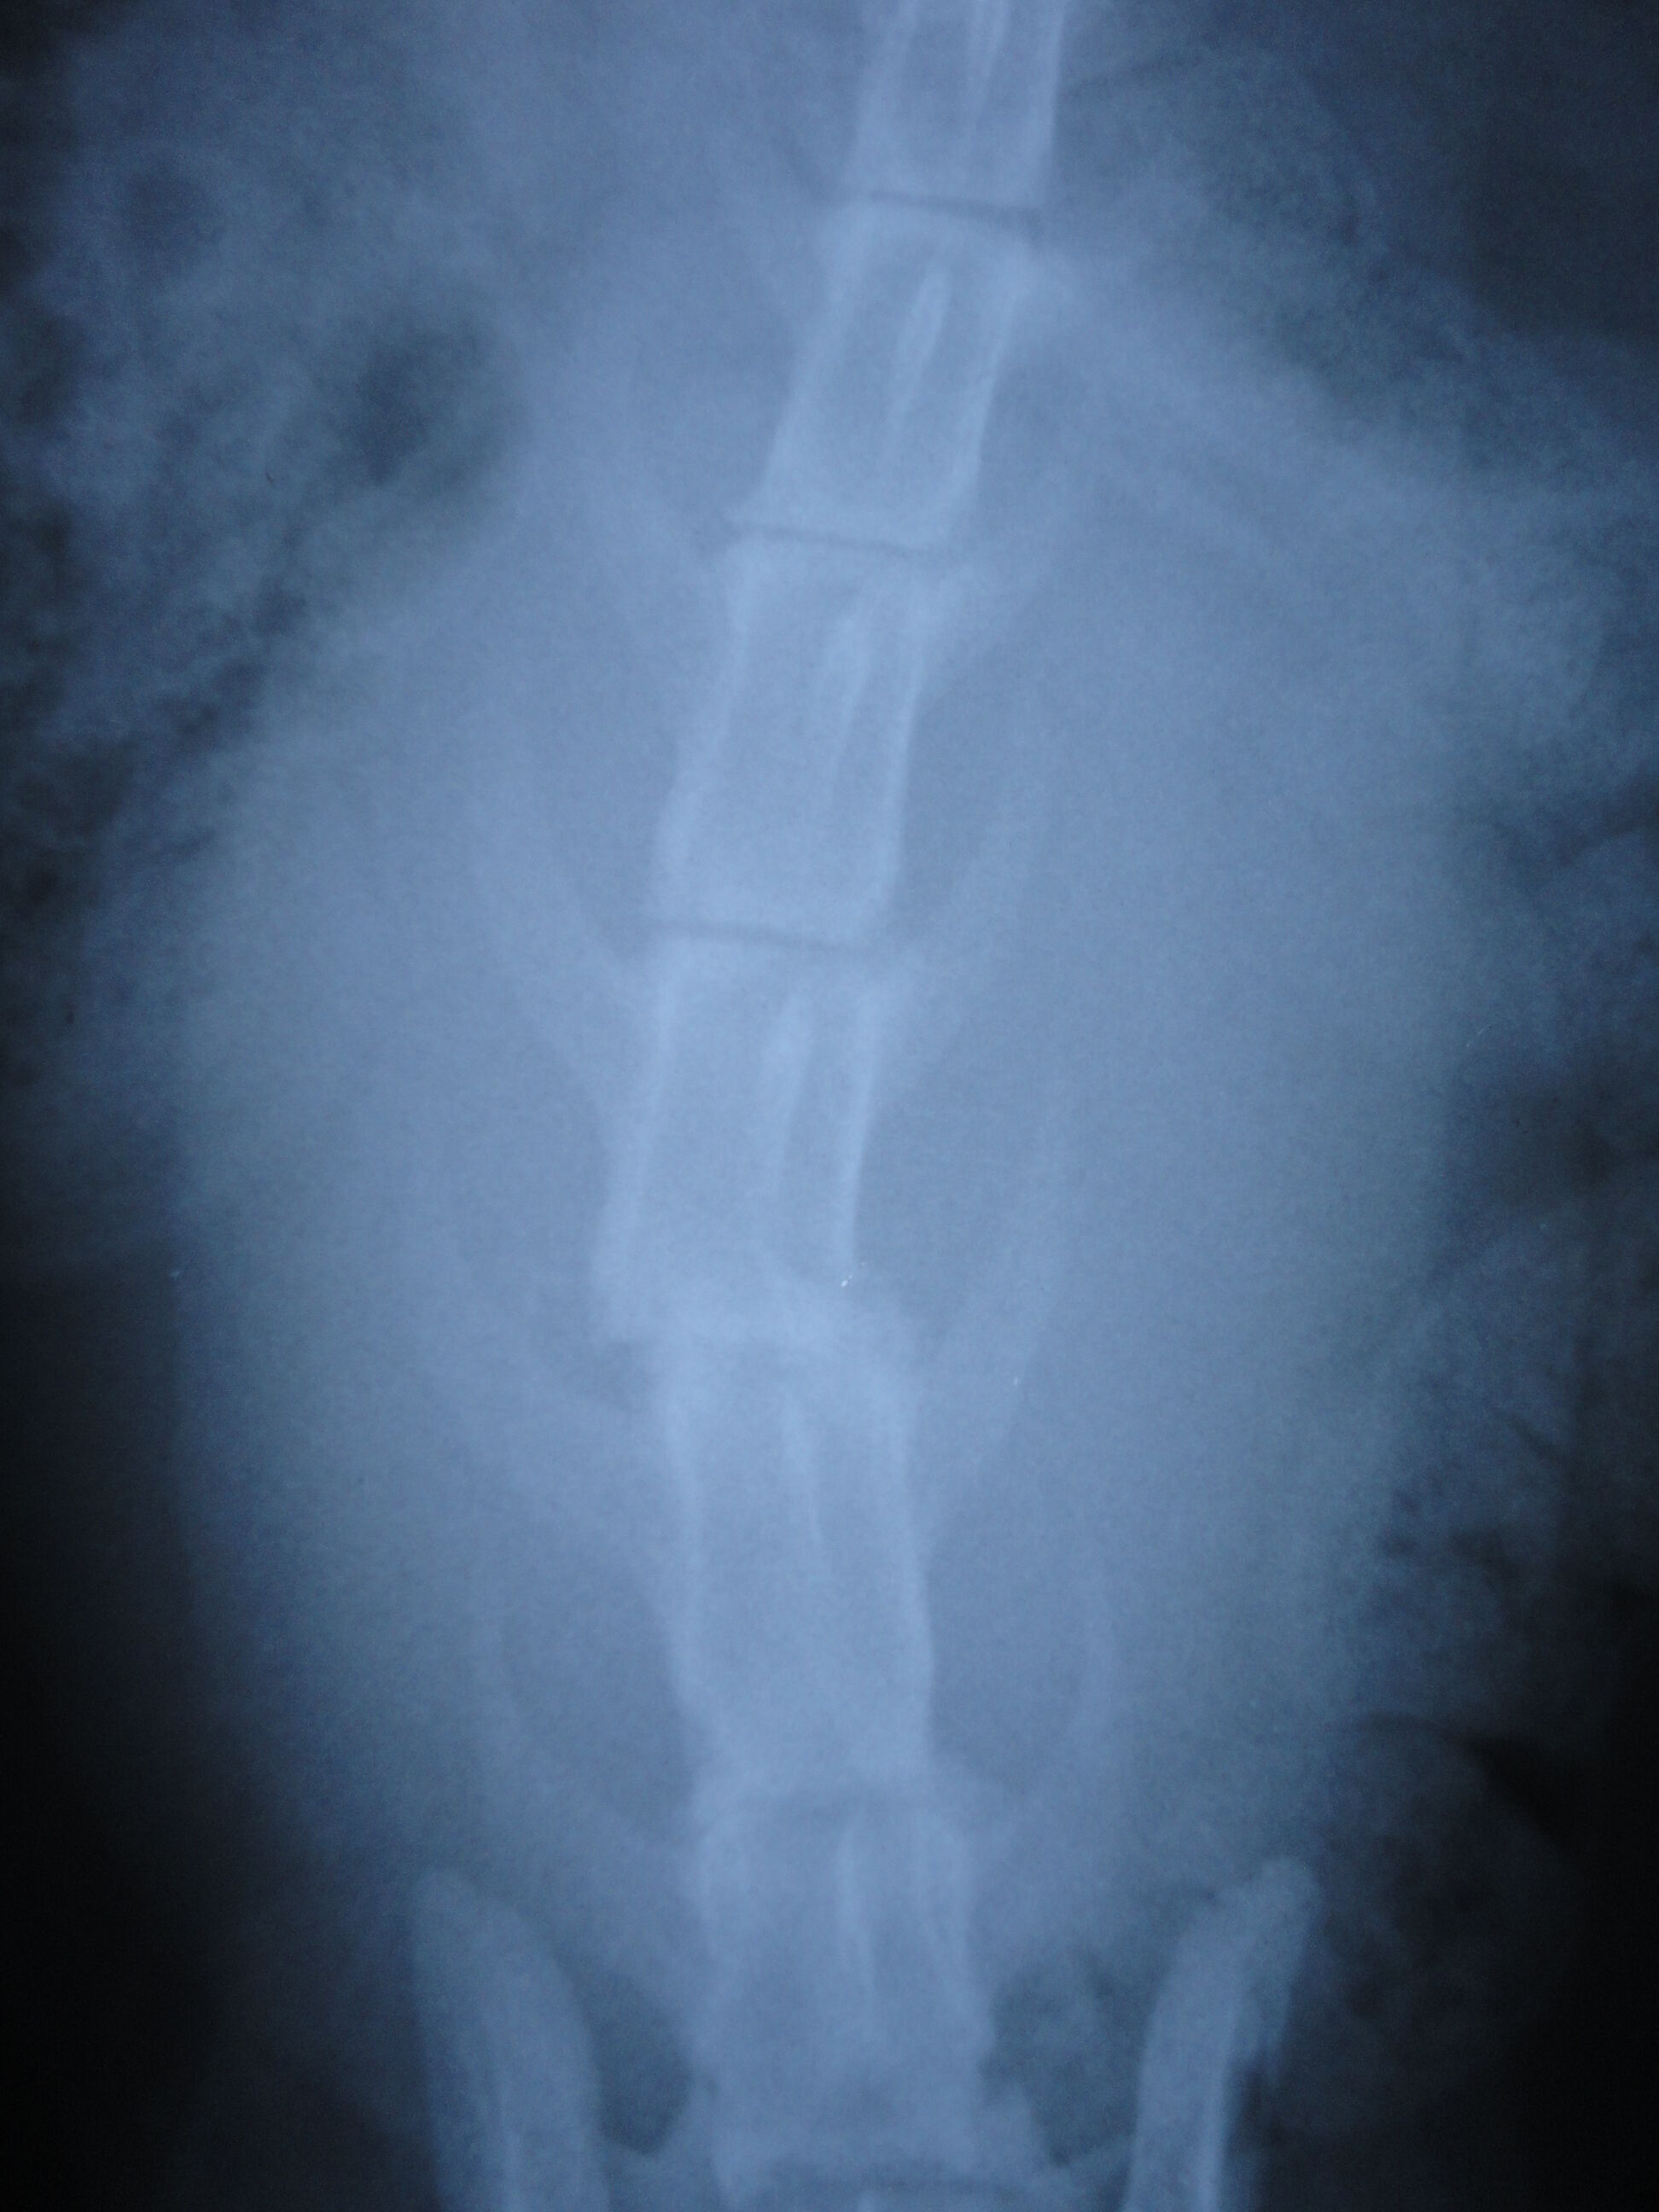

主題: 癱瘓貓 申請者姓名: 陳小玲 花色: 申請日期: 2012-12-30 21:13:43 申請者部落格: 申請者臉書網址: 所在縣市/合作醫院: 嘉義市/你我牠動物醫院 治療費用: 20500元 需求人數: 22人 已結案 (2013-02-23 14:27:24) 報名人員: caspper(已付款)、ninachan(已付款)、May Chuang(已付款)、花媽(已付款)、Juen-Nien Lin(已付款)、Juen-Nien Lin(已付款)、SHIN HUI(已付款)、曹小文(已付款)、曹小文(已付款)、曹小文(已付款)、曹小文(已付款)、曹小文(已付款)、曹小文(已付款)、曹小文(已付款)、曹小文(已付款)、曹小文(已付款)、曹小文(已付款)、曹小文(已付款)、曹小文(已付款)、曹小文(已付款)、曹小文(已付款)、曹小文(已付款)、 候補人員: 動物病情說明: 被車撞成了癱瘓貓.也可能是因為不能行走,拖著身體而掉入水溝,被發現時已奄奄一息,牠因為錯過黃金救援時間,要一輩子癱瘓了,現在在收費中途姐姐家,但仍然希望有人可以照顧牠.